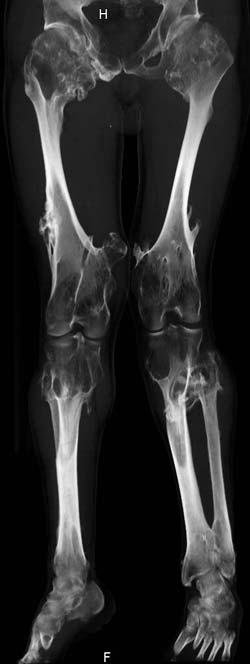

Oбратился больной 30 лет с хондродисплазией, множественными деформациями и экзостозами. Сгибательно-приводящие контрактуры Т/Б сустав, поясничный лордоз.

Интелектуально развит, работает програмистом. Болей нет. Анализы крови в пределах нормы, понижен кальций (общий Ca 1.62, N от 2.3 до 2.75; ионизорованный 0.67, N от 0.7 до 1.07) и щелочная фосфотаза -7.9. По данным КТ, оптическая плотность диафизов 150 - 200 NU (N в его возрасте 300 - 350NU) метафизарный остеопороз от 100NU до отрицательных величин - 80 NU.

Больной настоятельно просит об исправлении деформаций и удаления экзостозов области коленных суставов.

30 years old male with chondrodysplasia and multiple exostoses admitted. Multilevel deformities, flexion-adduction limitation of hip ROM, lumbar lordosis. Intellectually developed, working in some software company. Painless. Blood tests are normal, except low Calcium (total serum Ca 1. 62, N is 2.3 - 2.75; ionized 0.67 N is 0.7 -1.07) and low alkaline phosphatase 7.9. Diaphysis bone density is about 150 - 200 NU (N in his age is 300 - 350NU). Metaphis osteoporosis is from 100NU to minus 80 NU.